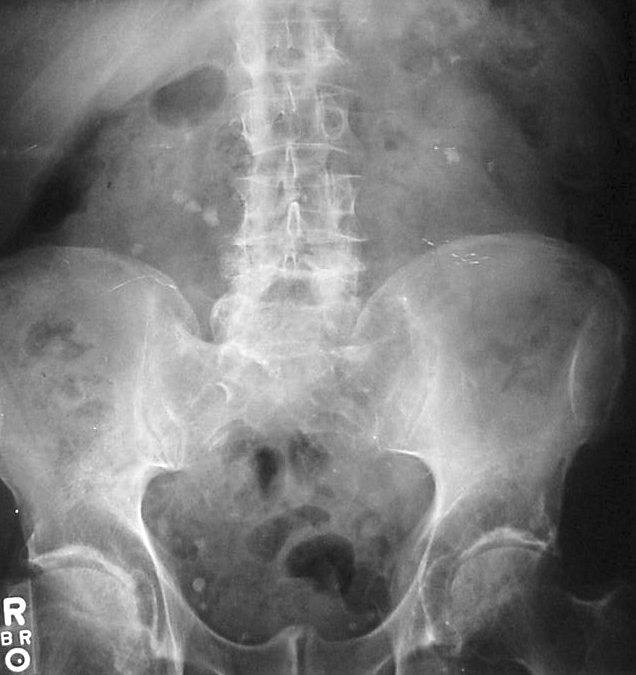

Nephrolithiasis

Nephrolithiasis is the formation of a stone from a urine solute.

Risk factors for nephrolithiasis include:

- Low urine volume

- High solute concentration in the urinary filtrate

Nephrolithiasis presents as:

- Colicky pain

- Hematuria

- Tenderness on one flank

Stone(s) normally passes within a few hours.

If the stone does not pass by itself, medical or surgical intervention may be necessary.